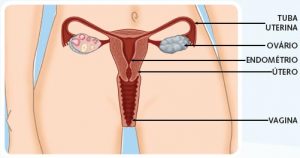

Para sabermos como prevenir, como cuidar, precisamos, como sempre, conhecer a doença. A doença que afeta cerca de seis milhões de brasileiras é caracterizada pela presença do endométrio fora da cavidade uterina; pode ser nas trompas, ovários, etc. Toda vez que o sangue migra no sentido oposto ao natural durante a menstruação, células se proliferam em outras regiões, o que faz com que haja tecido do endométrio fora do útero.

O endométrio é um tecido que reveste internamente o útero e ele fica todos os meses mais espesso, ‘’esperando’’ que haja algum sinal de fecundação. Quando a gravidez não ocorre, esse tecido mais espesso descama e é expelido, o que conhecemos como menstruação.

O endométrio é um tecido que reveste internamente o útero e ele fica todos os meses mais espesso, ‘’esperando’’ que haja algum sinal de fecundação. Quando a gravidez não ocorre, esse tecido mais espesso descama e é expelido, o que conhecemos como menstruação.